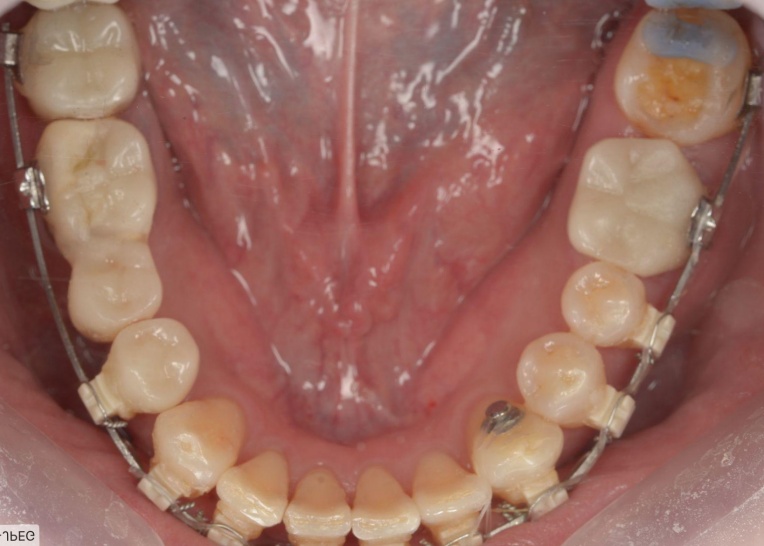

まず、ワイヤー矯正装置を用いた矯正治療を開始します。

折れている歯を一時的に利用しながら、受け口傾向にある噛み合わせが改善するよう、歯の位置を少しずつ調整していきました。

矯正治療中は定期的に来院いただき、装置の調整を行います。

歯や歯茎の状態、噛み合わせの変化を確認しながら、目標とする歯並びと噛み合わせに近づくよう治療を進めました。

矯正治療終了後は、整えた歯並びが後戻りしないよう、細いワイヤーを固定して歯並びを安定させる装置「リテーナー」を装着しました。

治療中